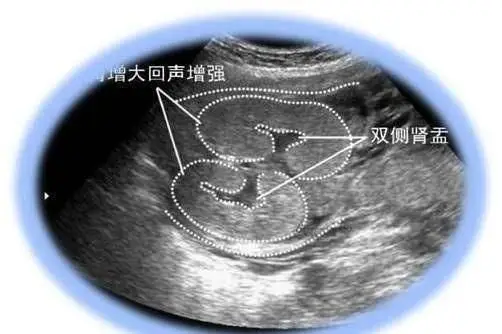

怀孕6个月胎儿双侧肾盂未见分离到底是男孩还是女孩